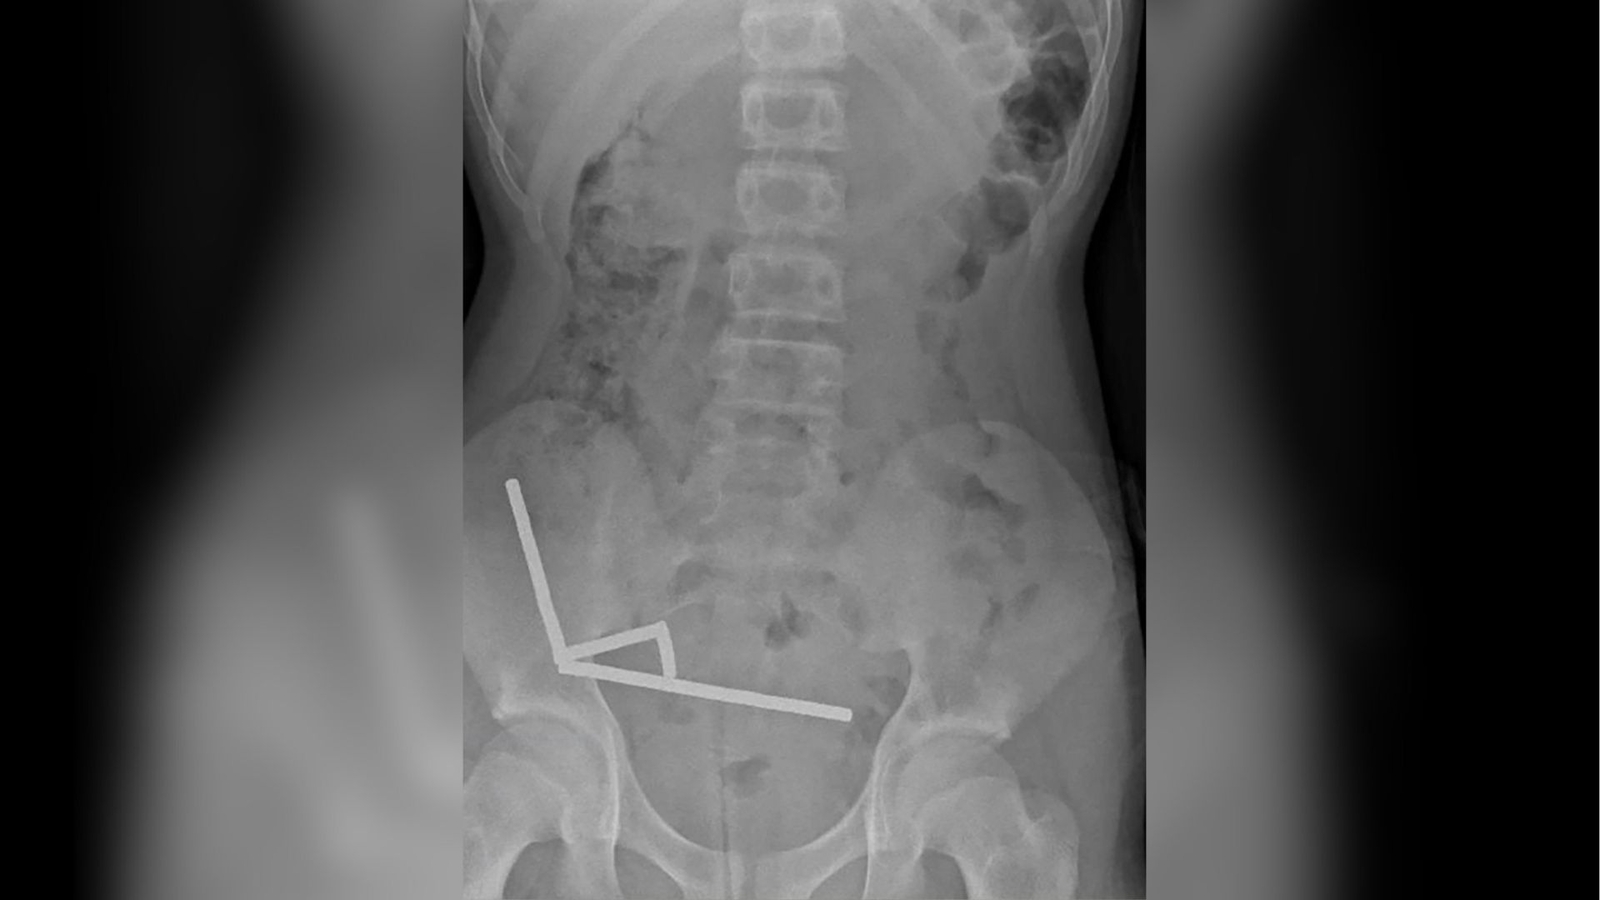

Boy hospitalized after swallowing dozens of high-powered magnets

A 13-year-old boy in New Zealand was hospitalized after swallowing dozens of high-powered magnets, ultimately losing part of his bowel, according to a recent case report in the New Zealand Medical Journal. The boy, whose identity was not...